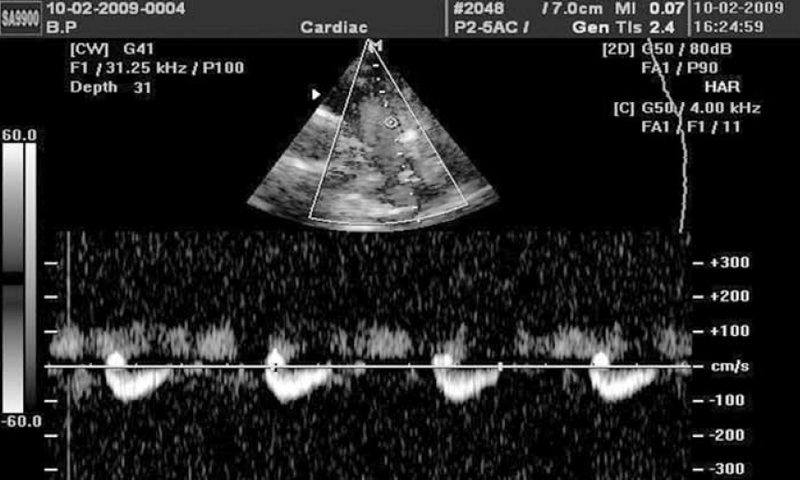

Диастолический сброс крови через коронарную фистулу в легочную артерию при постоянно-волновом допплеровском картировании отчасти напоминает аналогичный сброс через ОАП, однако является более низкоскоростным и менее продолжительным по времени, не занимая весь диастолический промежуток на допплерограмме (см. рис. 6).

Рис. 6. Диастолические потоки, отражающие сбросы крови через коронарную фистулу в ствол легочной артерии, визуализируются в секторе положительных значений над изолинией между систолическими и могут симулировать допплерограмму при классическом открытом артериальном протоке